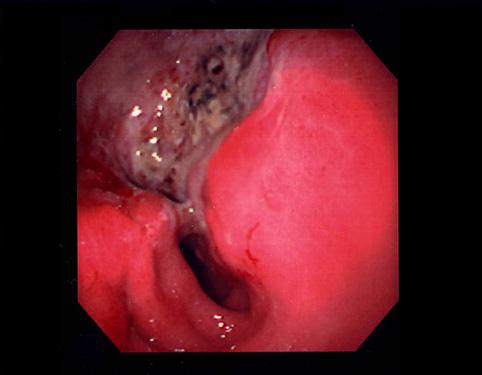

Criteria of Hist.ClassificationMalignant epithelial tumor/Adenocarcinoma

LocationStomach/Antrum

Technique, MethodEndoscopy

Macroscopic TypesType 3 Ulcerated type with infiltration/

Size40 -

Depth of Tumor Invasionserosa (adventitia)